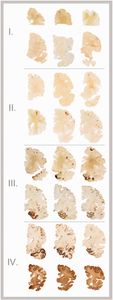

| 2013 | The Spectrum of Disease in Chronic Traumatic Encephalopathy

Led by Dr. Ann McKee, this paper described the McKee staging scheme for CTE pathology. Analyzing a cohort of 85 brain donors exposed to repetitive head impacts (RHI), Dr. McKee and researchers developed a progressive staging scheme for CTE on a I-IV scale, with each increasing stage corresponding to more severe and widespread pathology. The paper also described clinical symptoms commonly observed in brain donors exposed to RHI.

| Characterizing Tau Deposition in Chronic Traumatic Encephalopathy (CTE): Utility of the McKee CTE Staging Scheme

Drs. Ann McKee, Michael Alosco, Jonathan Cherry, and colleagues published this paper which outlined and validated the 2013 McKee staging scheme for CTE pathology in 366 male brain donors exposed to RHI from the UNITE Brain Bank. The findings lent additional support to the application of the McKee staging scheme for CTE and highlighted the regional distribution of phosphorylated tau in CTE.